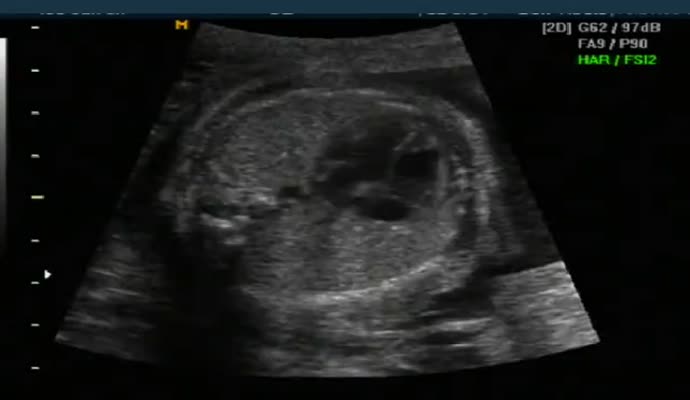

아래는 초음파 영상이기는 하지만 그렇게 올려진 영상 샘플입니다.

여러분들이 자신의 아기와 좀더 적극적으로 소통하도록 하려는 목적과 함께 병원 홈피의 내용도 충실히 하고 또 보시는 분들로 하여금 임신과 출산을 좀더 긍정적이고 감동적으로 받아들이게 하고자 하는 목적도 있아오니 여러분들께서 많이 참여해 주시면 좋겠습니다.